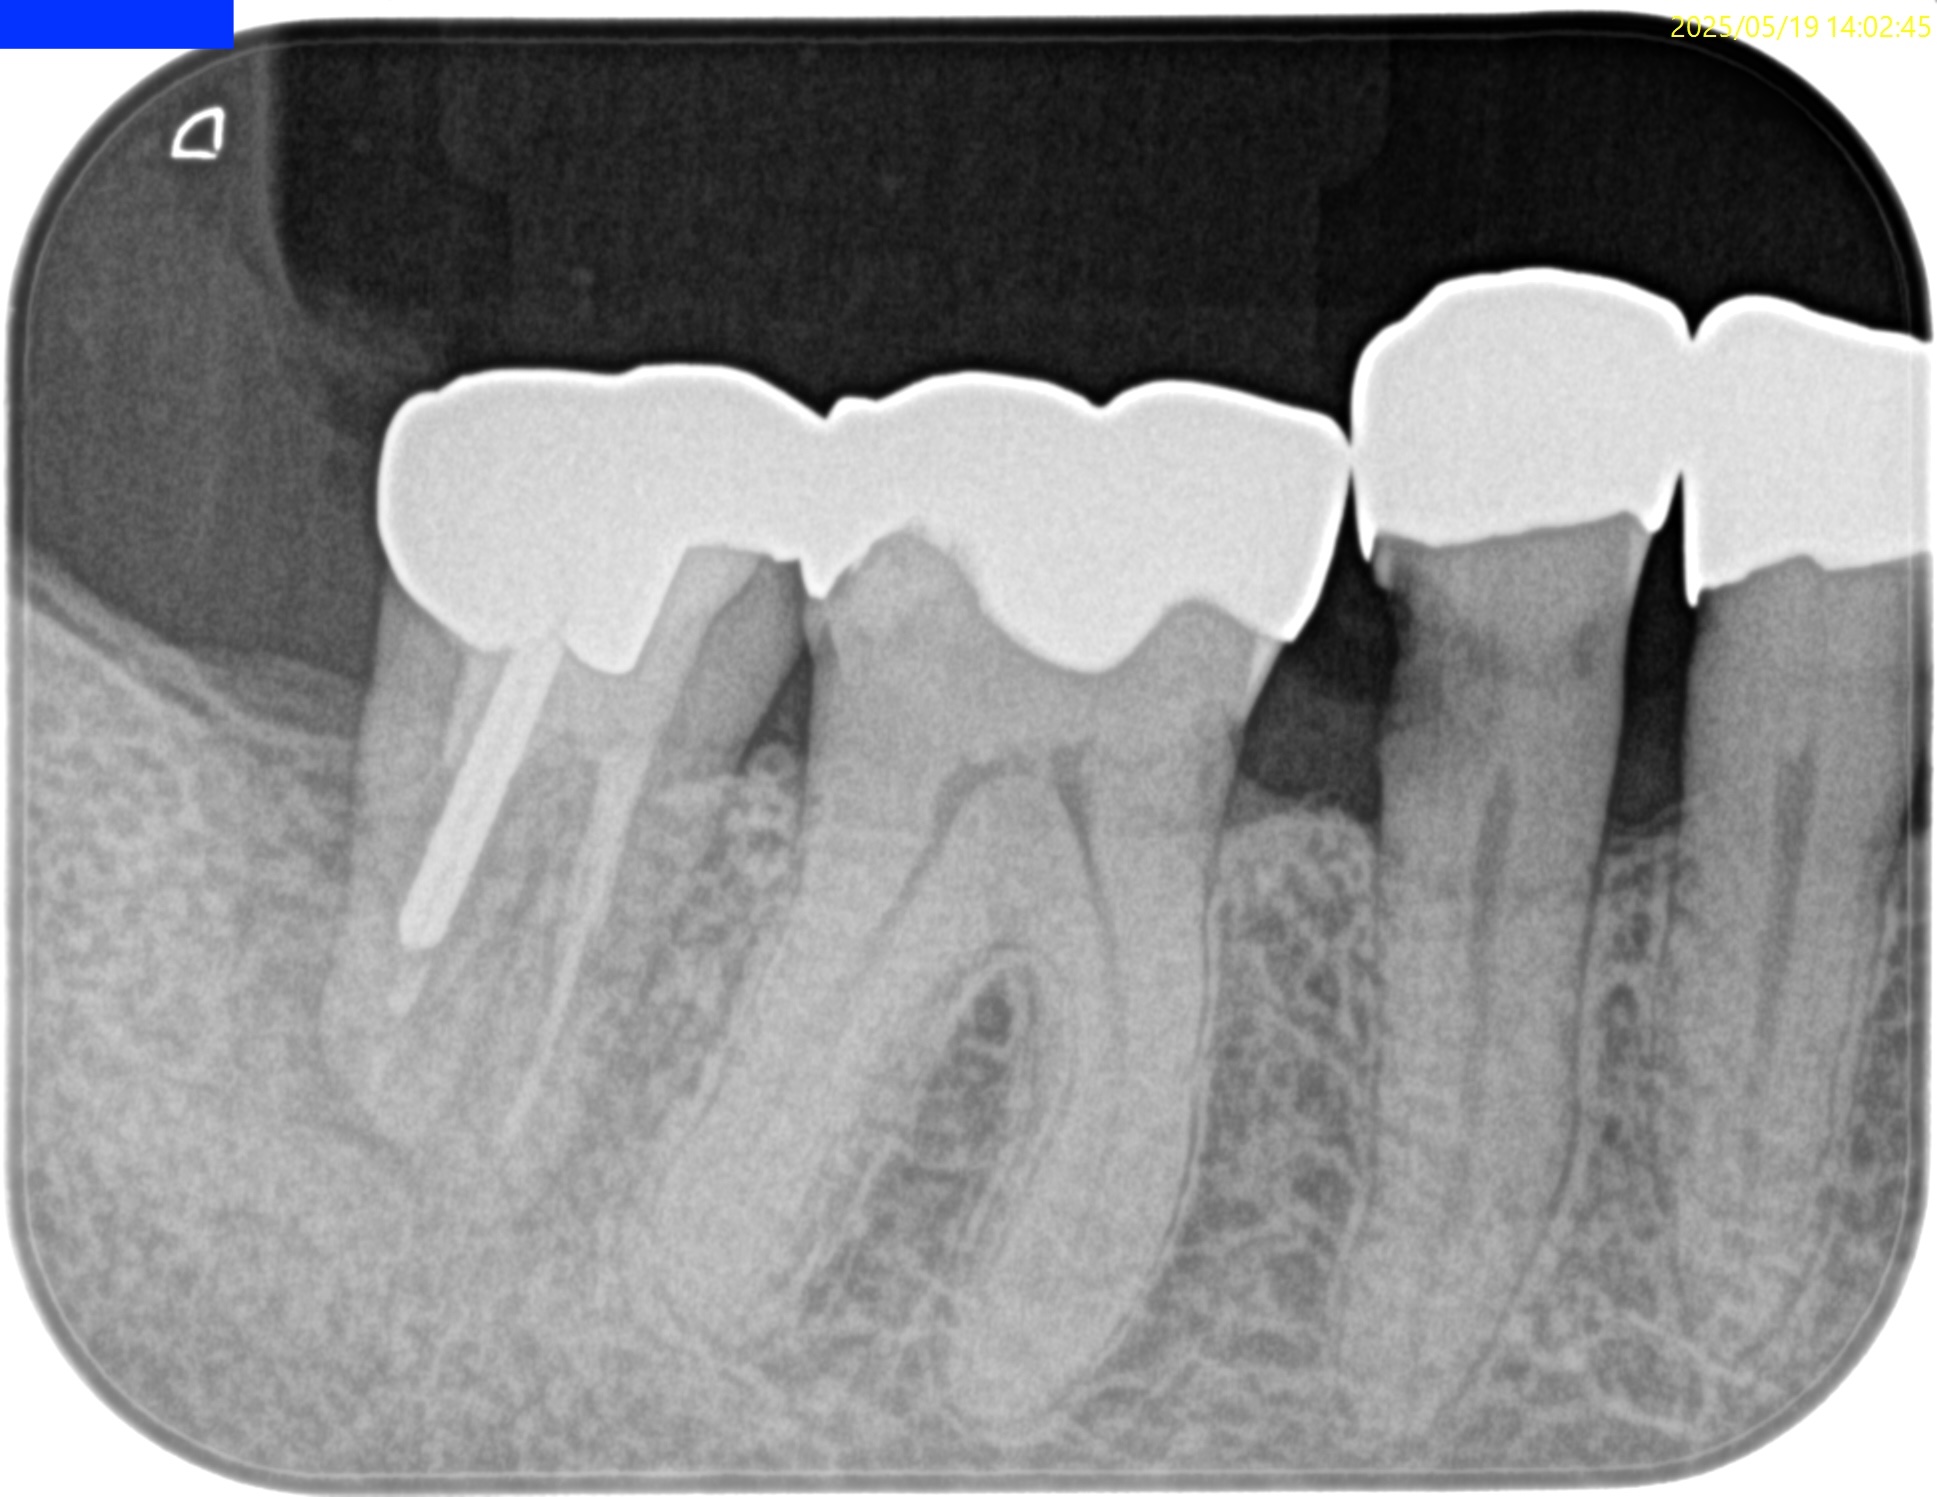

PA(2025.6.25)

検査でなく、PAで初めて患歯が#29だとわかる。

歯髄に迫る大きな虫歯が保険の修復物の下部にある。

これが保存できるだろうか?